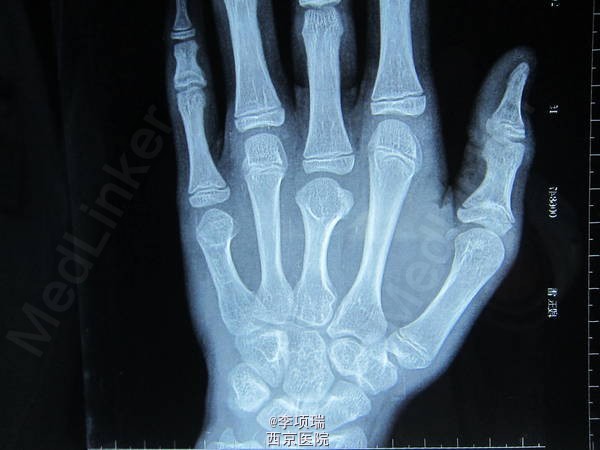

你见过这样的畸形吗?

患者15岁,男性。这个患者大家看怎样手术?何时手术?